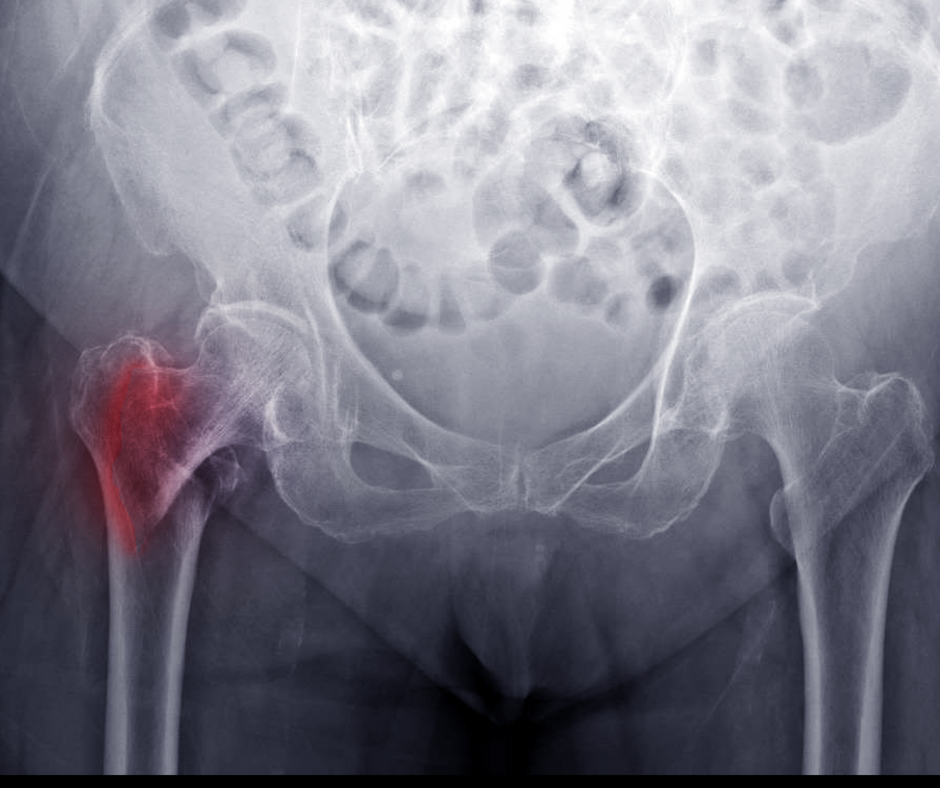

The authors of a new meta-analysis found no significant differences between clinicians and artificial intelligence in diagnosing fractures but conceded that slightly over half of the studies assessed had a high risk of potential bias.

What is your diagnosis?